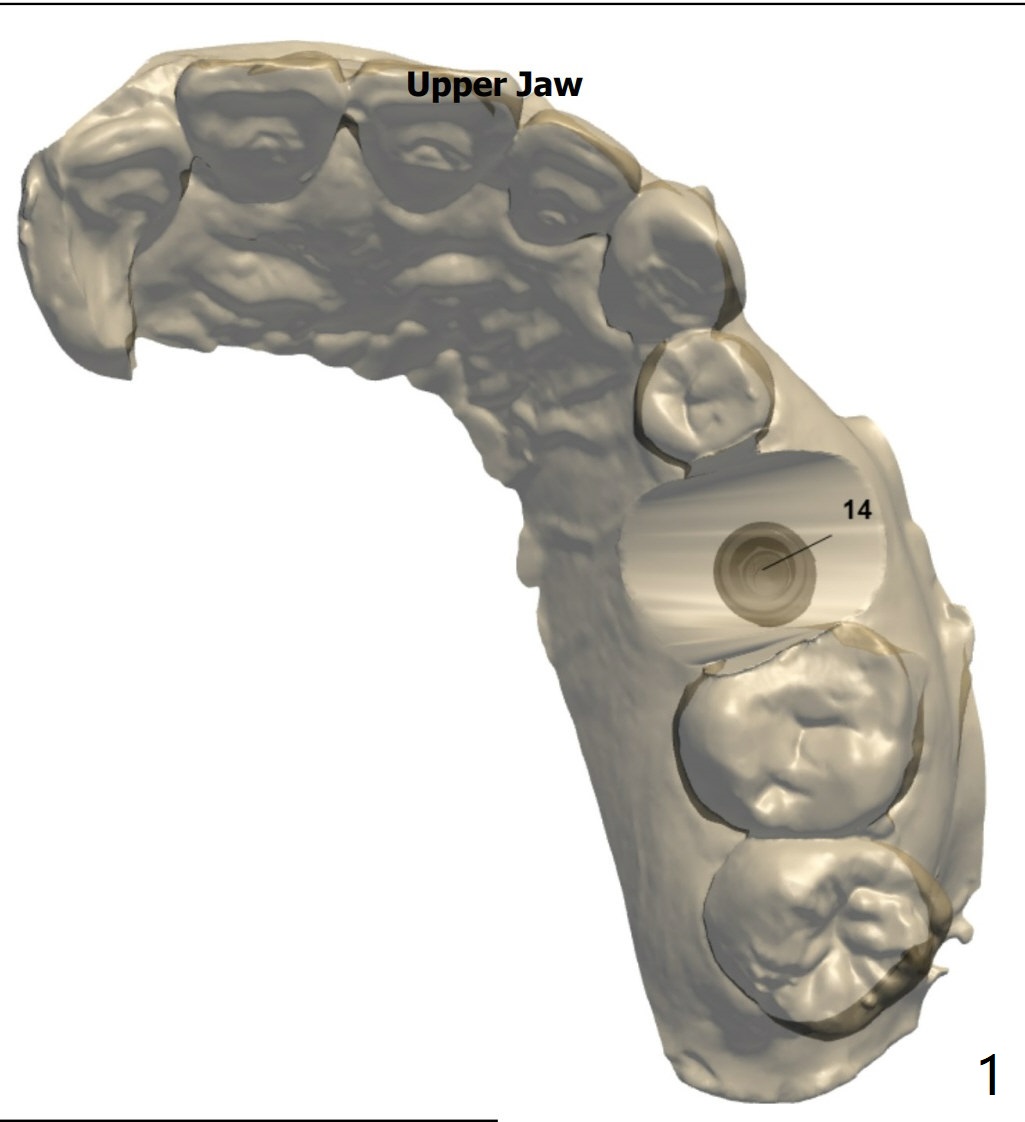

即刻种植与提升

粘性骨粉